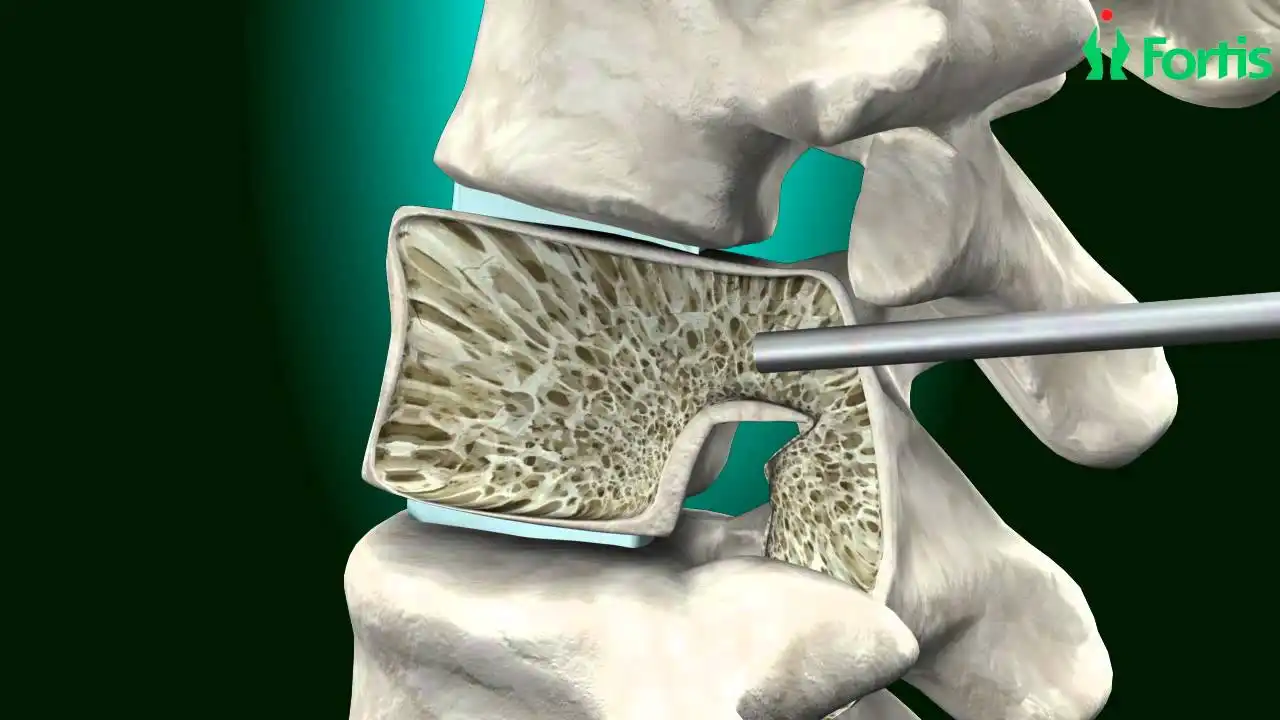

جدیدترین روش ترمیم رباط صلیبی زانو | آرتروسکوپی مدرن 1405 با کمترین درد و سریعترین بهبودی برای تمامی بیماران ادامه مطلب »